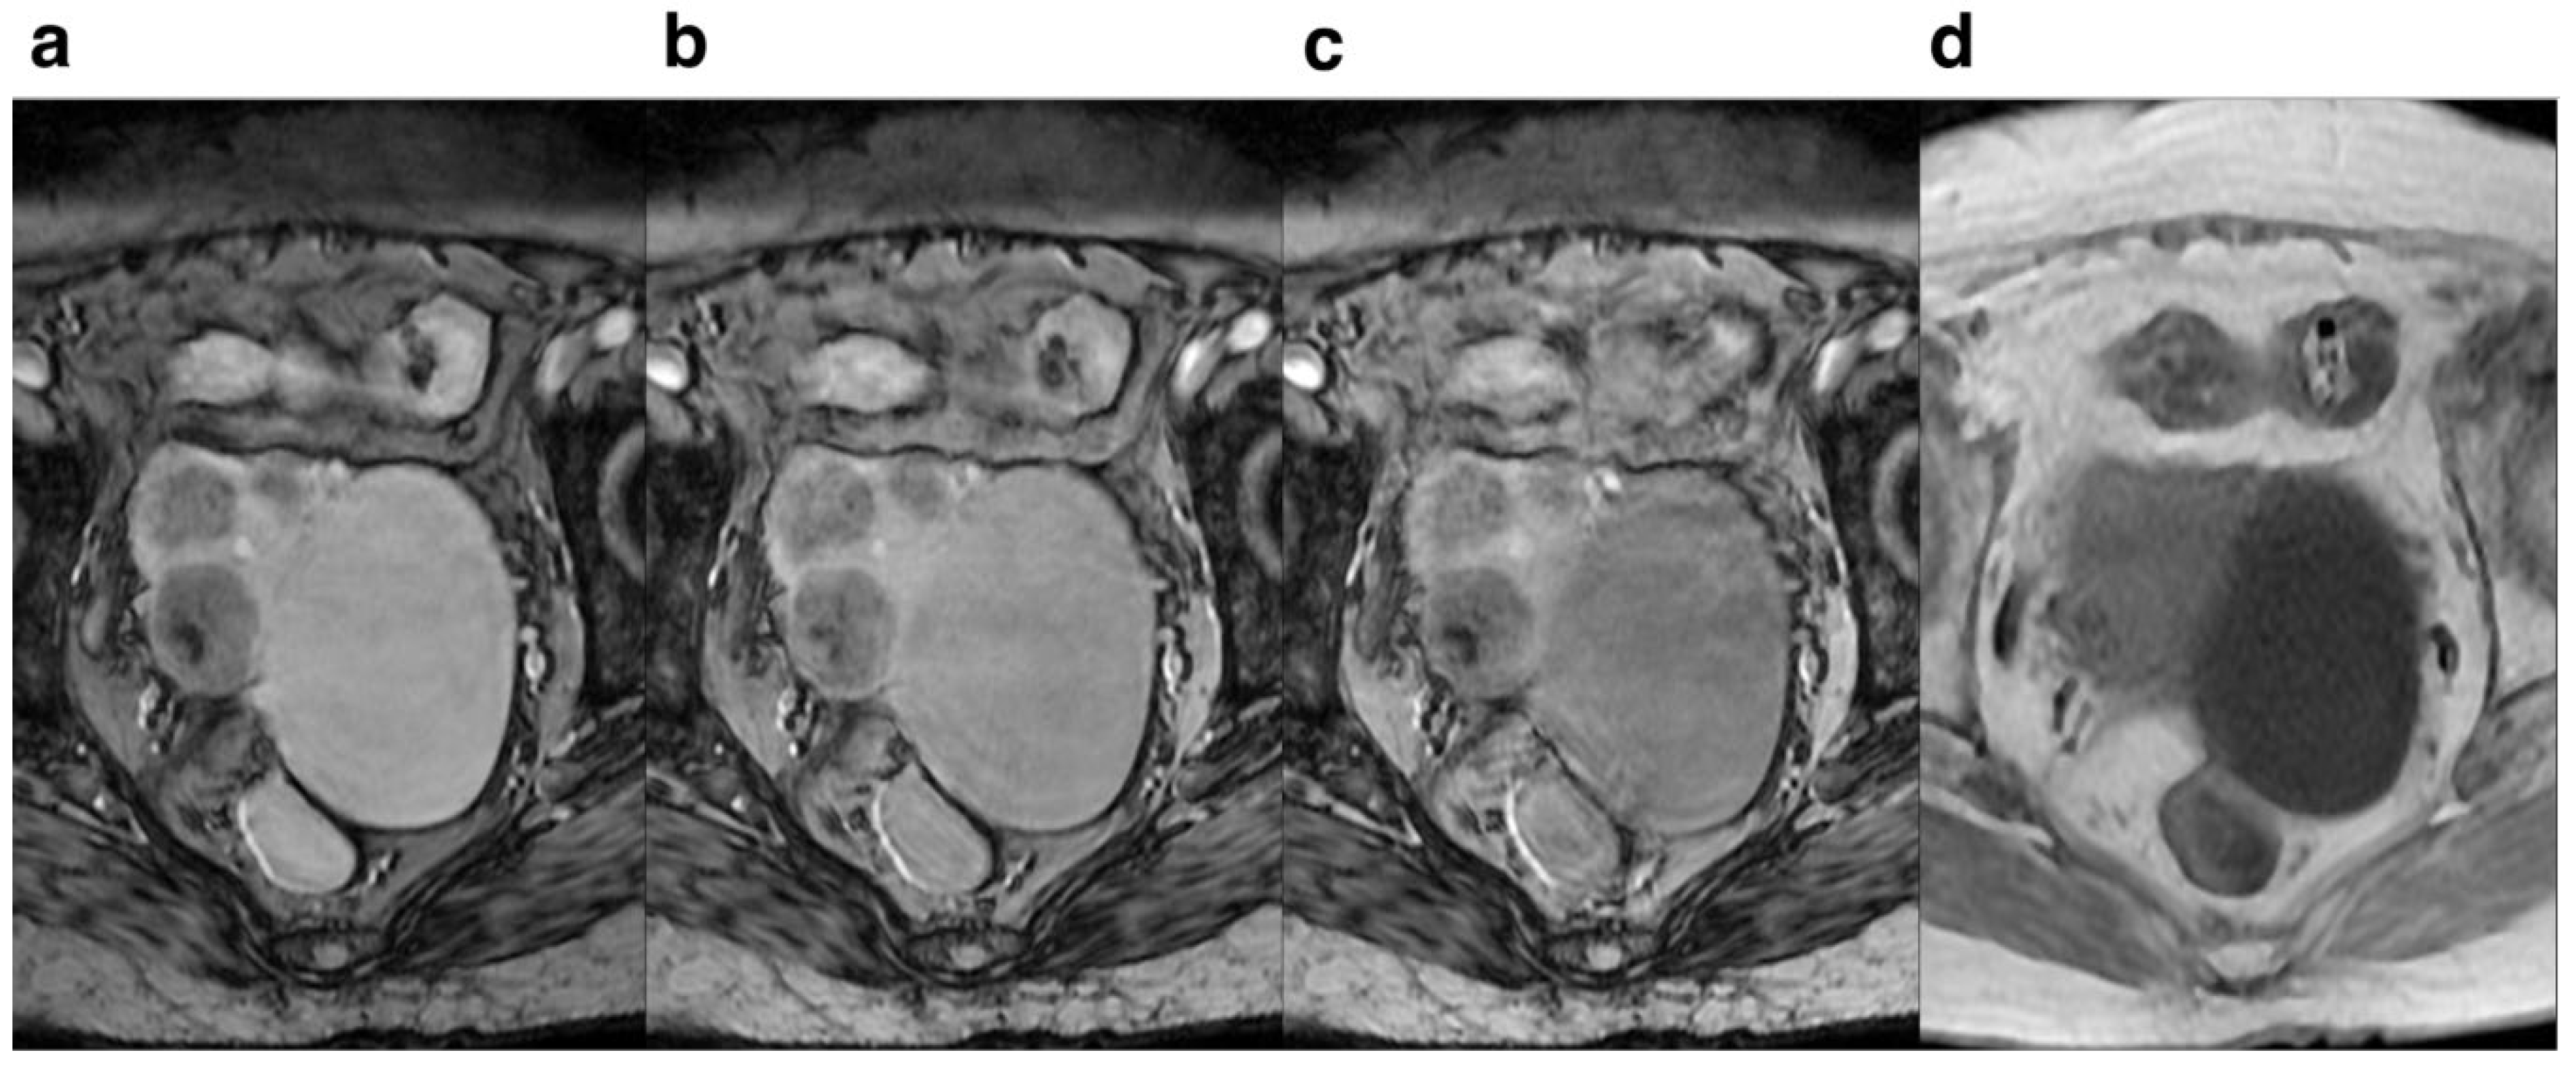

Figure 3. Female, 30 years old. Pelvic cavity under each FA is shown. SWI sequences FA were 10° (a), 15° (b), 20° (c),and T1WI(d) respectively.It can be seen that when FA=10°, the pelvic structure is more clearly displayed and the lesion is more clearly outlined than the other FA.

Regarding FA, lower FA revealed more anatomical detail and lesion clarity, less deformation and artifacts, and 10° had the best effect compared to 15° and 20°. The score for anatomical details and lesion clarity for FA=10° were significantly higher compared to those of FA=15° and 20°, indicating that the anatomical details and lesion clarity were highest at 10° (Figure 3). For the degree of deformation and ghosting, the subjective rating for FA=10° was higher than that of FA=15° and 20°, suggesting that the degree of deformation and ghosting was smallest at 10° (Figure 4), while the degree of deformation and ghosting was the most severe at 20°. Qualitative assessment revealed superior image quality at a FA of 10° compared to 15° and 20°. Images acquired at FA=10° demonstrated improved visualization of small hemorrhagic lesions, clearer delineation of peritumoral infiltration in tumors, and enhanced depiction of pelvic anatomical structures. Moreover, image quality was superior in the FA=10° scans compared to FA=15° and 20° scans, likely attributable to the substantial difference in signal intensity between focal lesions and surrounding tissues. This heightened level of detail is crucial for accurate diagnosis and selection of optimal treatment strategies.